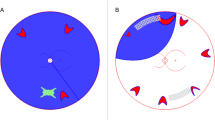

Input Data The data was collected from OGI dataset was included 301 patients with 12 features as prognostic factors including: Age, Sex, Type, Grade VA (Initial VA grade), Relative Afferent Pupillary Defect (RAPD), Zone, Traumatic Cataract, Traumatic optic Neuropathy (TON), Intraocular Foreign Body (IOFB), Retinal Detachment (RD), Endophthalmitis, and OTS grade. More descriptions and related images of dataset features are provided in Table 1; Fig. 1.